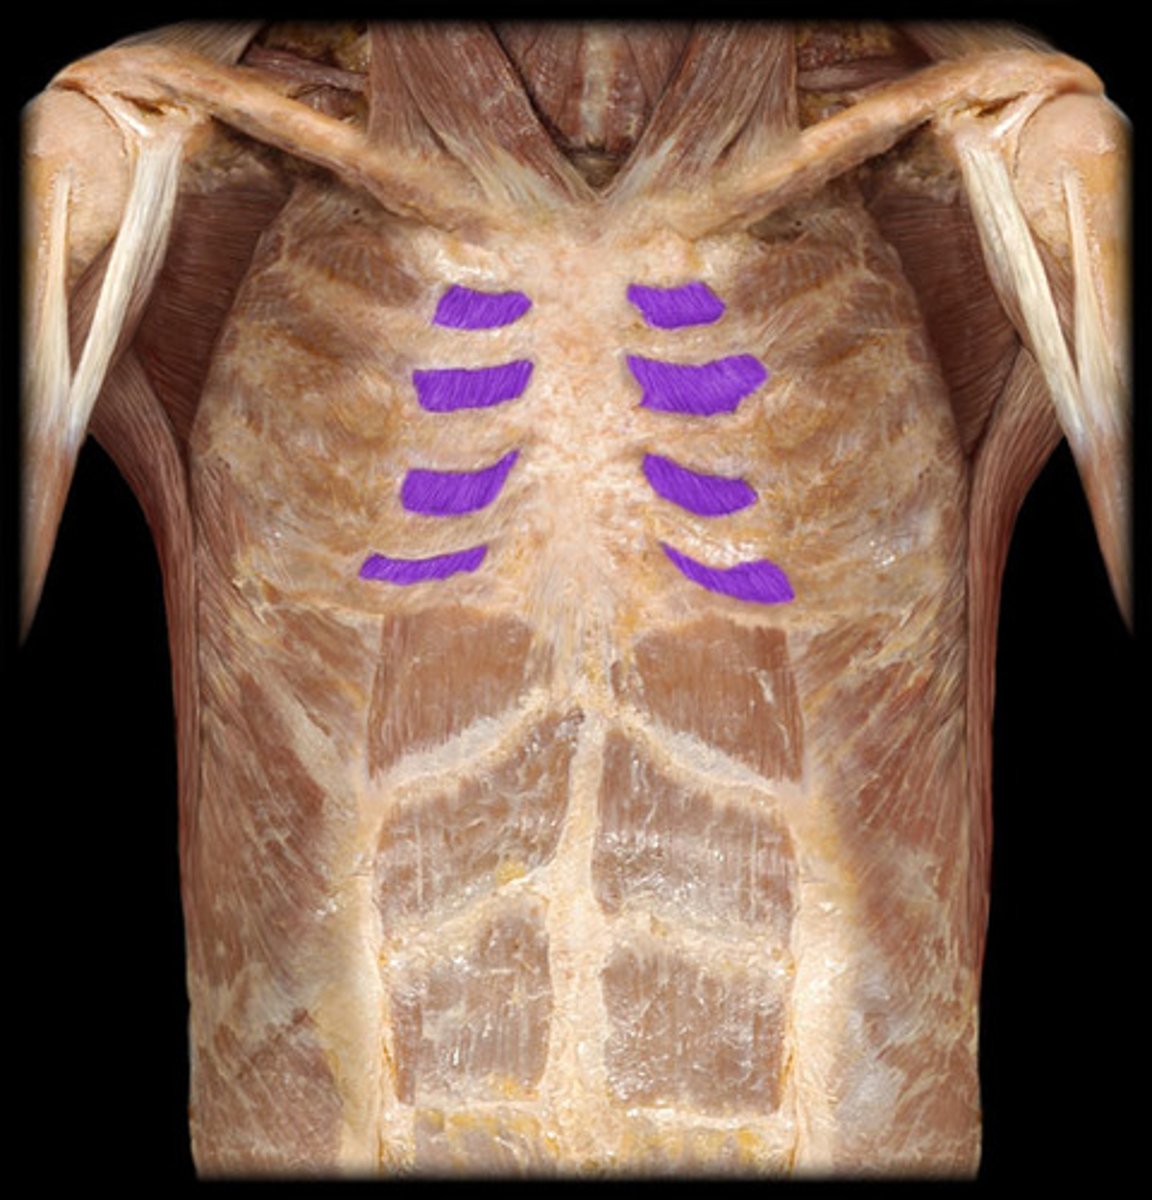

Erector Spinae

Diaphragm

Internal intercostals

External intercostals